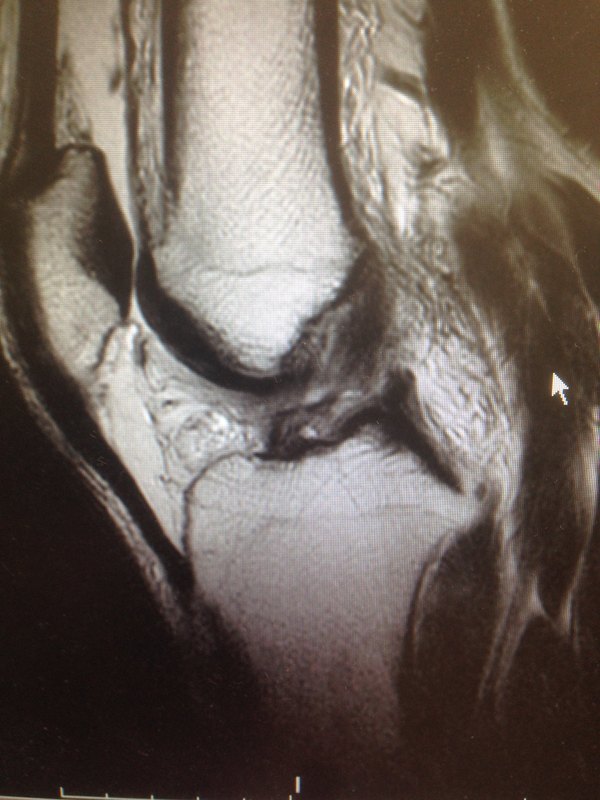

左膝外傷后兩天就診,查體前抽屜實(shí)驗(yàn)陰性,lachman 實(shí)驗(yàn)止點(diǎn)軟性,核磁共振檢查結(jié)果顯示前交叉韌帶損傷,內(nèi)側(cè)半月板后角損傷,股骨髁及脛骨平臺(tái)骨挫傷。 建議行關(guān)節(jié)鏡檢查手術(shù)治療,術(shù)中見前交叉韌帶斷裂,前向穩(wěn)定左右喪失,內(nèi)側(cè)半月板后角縱裂,術(shù)中給予前交叉韌帶重建及半月板fastfix 縫合治療,術(shù)后按流程康復(fù)指導(dǎo),手術(shù)效果滿意,康復(fù)良好,恢復(fù)傷前運(yùn)動(dòng)能力!